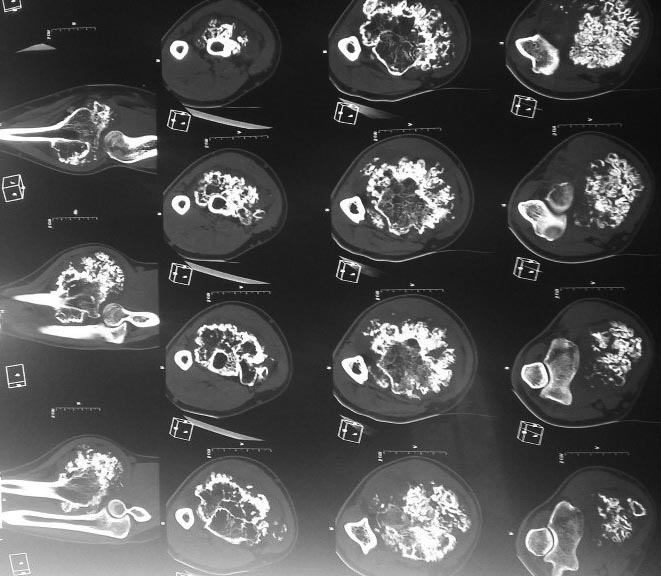

остеохондрома лучевой кости в проксимальном отделе |

Прошу помочь. обратился молодой человек 21 год с образованием правого предплечья. в течении 10 лет рост образования.

Гистологическая верификация - остеохондрома. в течении 2 лет он пытается найти клинику в которой он бы мог лечиться. Через минздрав Сахалинской области были направлены письма в различные клиники России. Отказ получен по всем клиникам кроме Илизарова. Но и там рекомендация по удалению опухоли по месту жительства... Я никогда этим не занимался, и коллеги то же отказываются. Нет опыта в лечении таких пациентов.